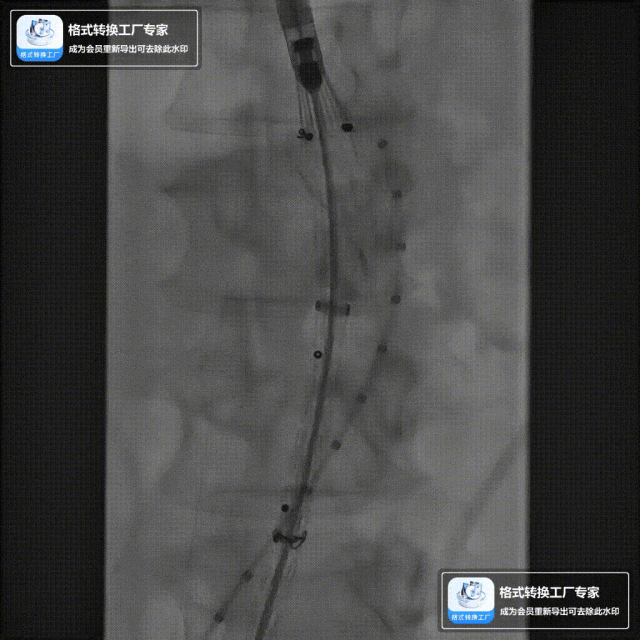

该技术主要适用于采用旋转式释放机制的支架。其核心操作步骤为:在主体支架释放出前2-3节后,轻微松开支架,然后反复反向旋转并上推输送鞘。 这一动作能促使已释放的近端支架段在瘤颈处产生可控的“堆叠”效应,从而更好地顺应瘤颈的弯曲形态,尤其是在大弯侧实现更紧密的贴壁,有效拓展了功能性密封区。

案例一(巨大成角瘤颈):患者瘤颈虽长但呈90度成角。在完成髂动脉重建后,采用Reverse技术释放主体支架。术中造影显示,支架完美贴合扭曲的血管大弯侧,术后一月复查CTA,原有的少量内漏已完全消失。

案例二(短瘤颈+梯形瘤颈):患者近端瘤颈长度不足1cm,且伴有大量附壁血栓。选用适当oversize的支架,结合Reverse技术释放,支架主体自动“寻找”并适应最佳的贴附区域,最终造影显示无明确内漏。